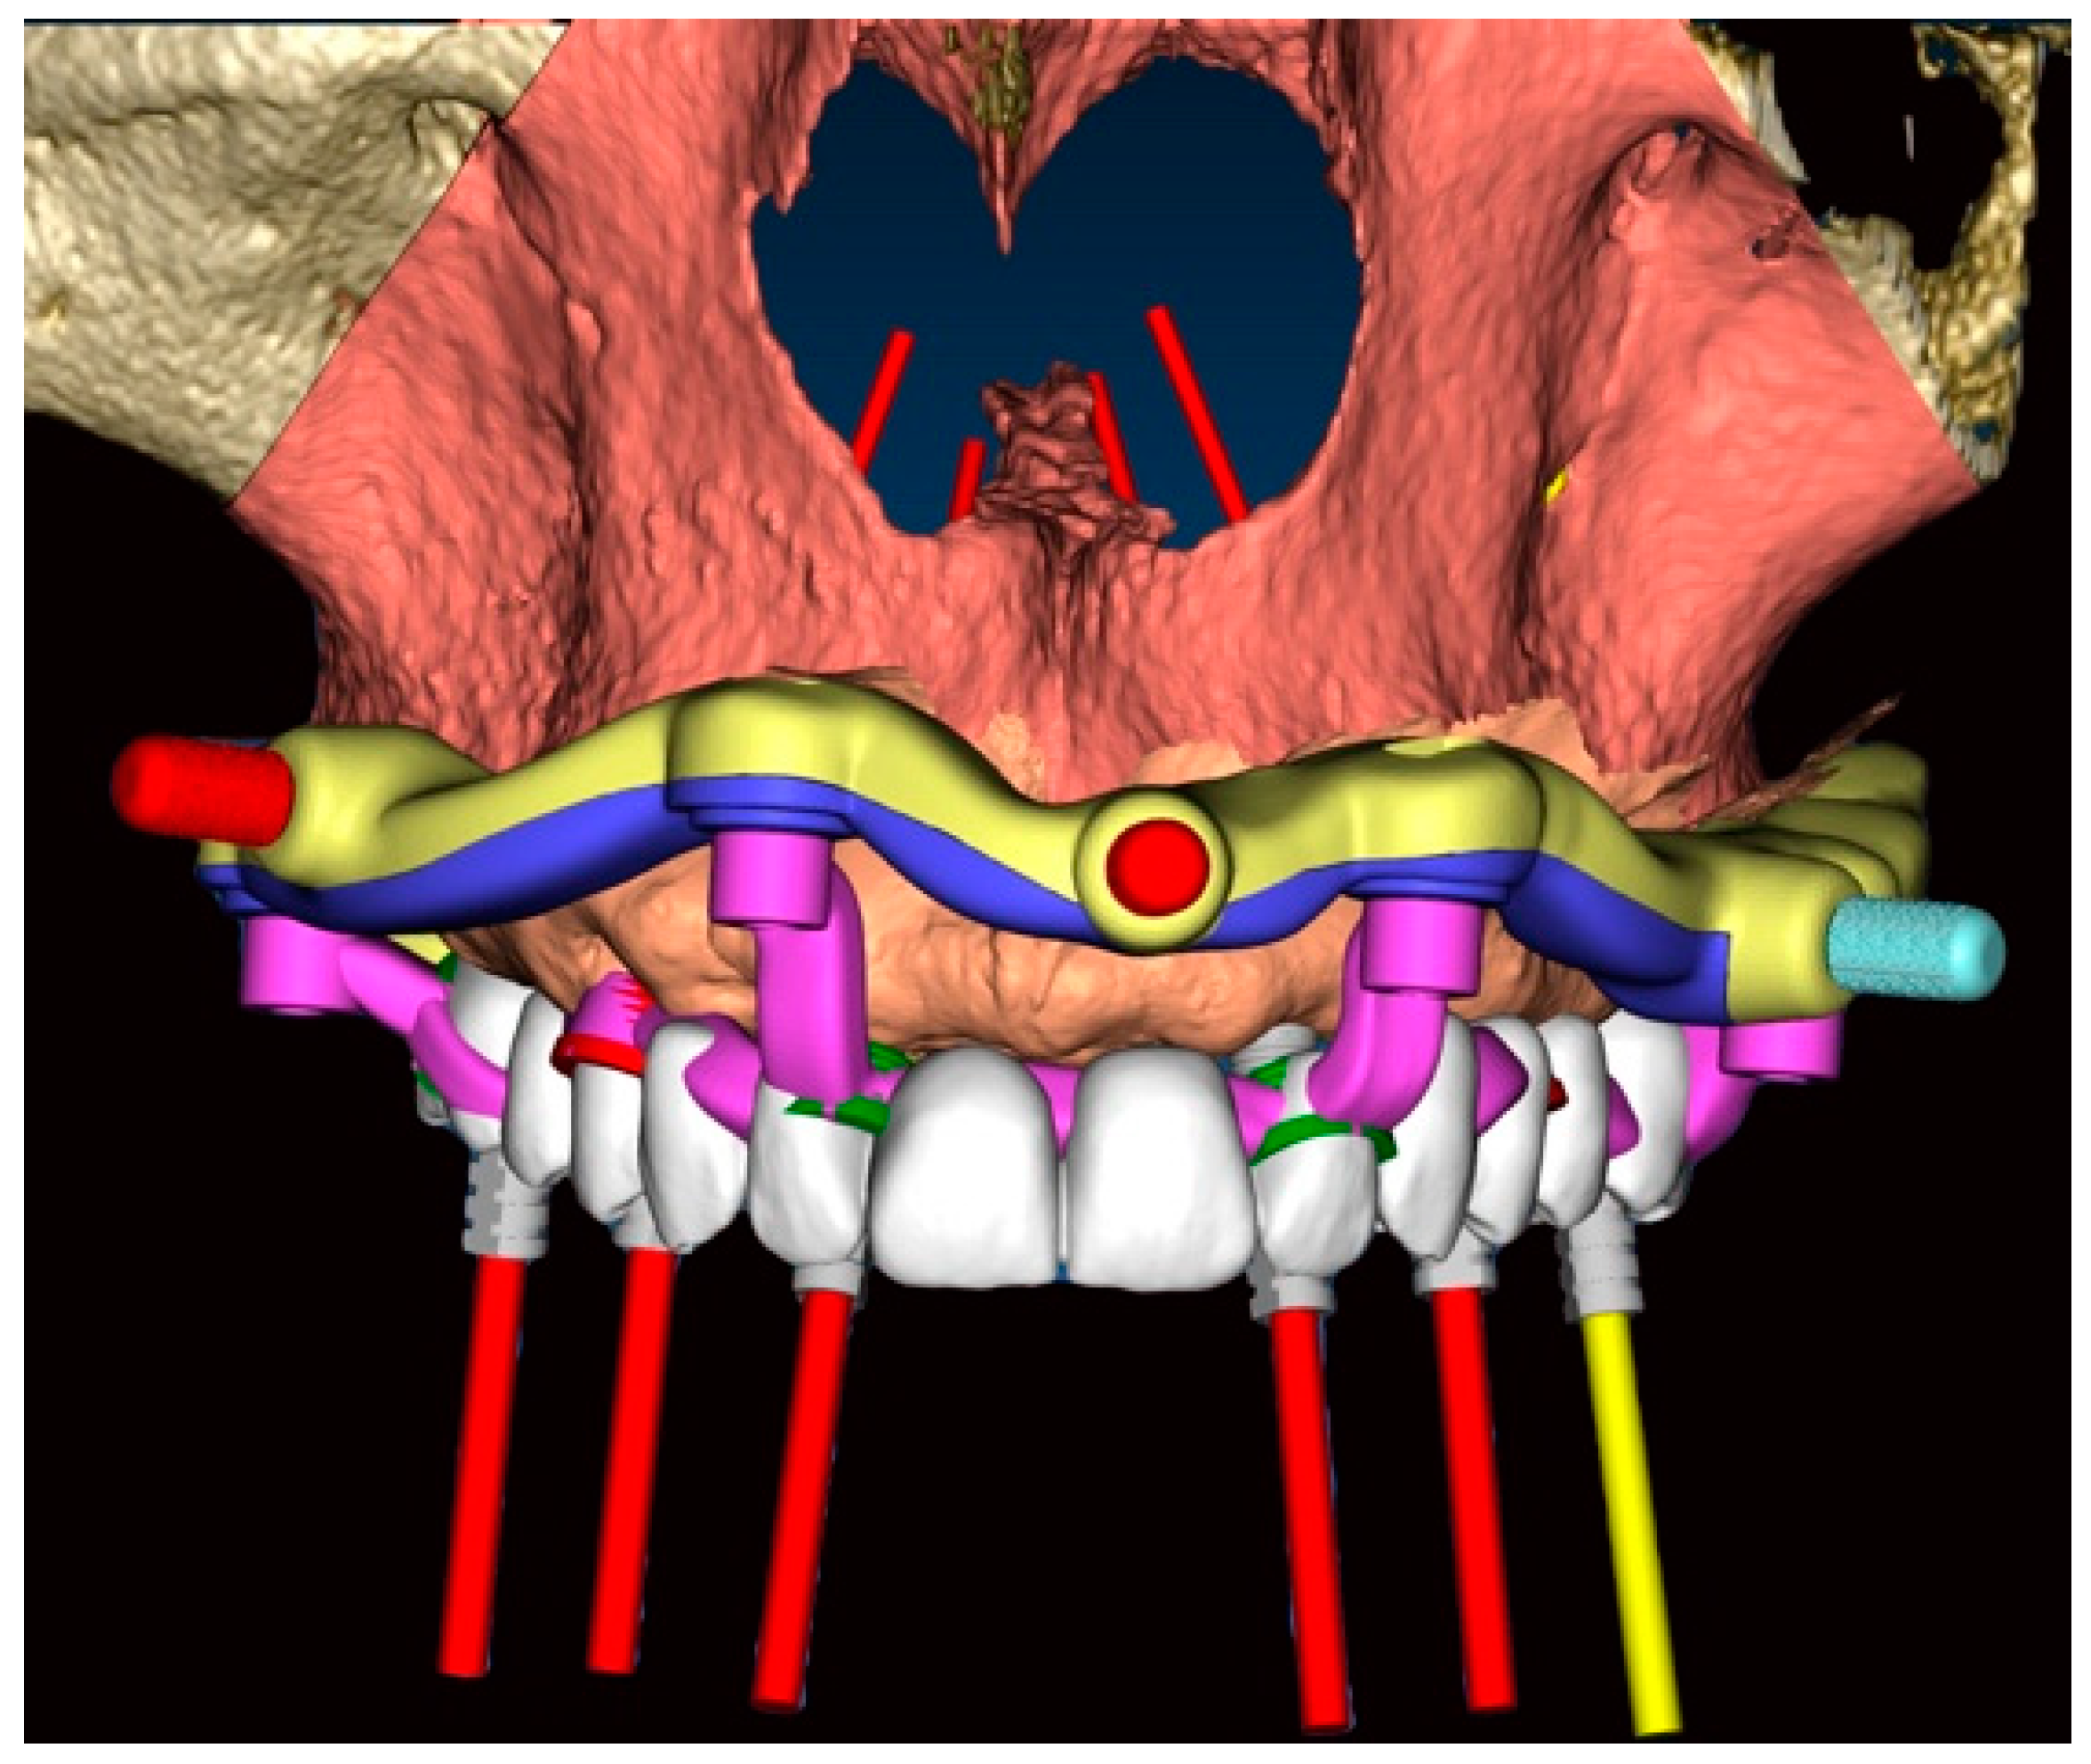

2. Materials and Methods

2.1. Surgical Planning

- 16: Oxy Implant FIXO Short 30° 4 × 10 mm

- 14: Oxy Implant FIXO Short 17° 4 × 10 mm

- 12: Oxy Implant FIXO Mini 17° 3.5 × 11.5 mm

- 22: Oxy Implant FIXO Mini 17° 3.5 × 13 mm

- 24: Oxy Implant FIXO Short 17° 4 × 11.5 mm

- 26: Oxy Implant FIXO Short 17° 4 × 8.5 mm

- Fixed component or base template: printed resin (Clear MED610™; Stratasys, Edina, MN, USA), reinforced with milled titanium grade 5 (SINERGIA DISK Ti; Nobil Metal, Bergamo, Italy).

- Removable components, screwed to the base template, consisting of:

- Positioning template: printed resin (Clear MED610™; Stratasys, Edina, MN, USA);

- Implant placement template (Figure 7): milled titanium grade 5 (SINERGIA DISK Ti; Nobil Metal, Bergamo, Italy);

- Provisional prosthesis: milled PMMA (Multilayer PMMA Disc; Dentsply Sirona, Verona, Italy) and a milled titanium grade 5 core (SINERGIA DISK Ti; Nobil Metal, Bergamo, Italy.